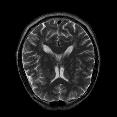

Recently, deep neural networks have greatly advanced undersampled Magnetic Resonance Image (MRI) reconstruction, wherein most studies follow the one-anatomy-one-network fashion, i.e., each expert network is trained and evaluated for a specific anatomy. Apart from inefficiency in training multiple independent models, such convention ignores the shared de-aliasing knowledge across various anatomies which can benefit each other. To explore the shared knowledge, one naive way is to combine all the data from various anatomies to train an all-round network. Unfortunately, despite the existence of the shared de-aliasing knowledge, we reveal that the exclusive knowledge across different anatomies can deteriorate specific reconstruction targets, yielding overall performance degradation. Observing this, in this study, we present a novel deep MRI reconstruction framework with both anatomy-shared and anatomy-specific parameterized learners, aiming to "seek common ground while reserving differences" across different anatomies.Particularly, the primary anatomy-shared learners are exposed to different anatomies to model flourishing shared knowledge, while the efficient anatomy-specific learners are trained with their target anatomy for exclusive knowledge. Four different implementations of anatomy-specific learners are presented and explored on the top of our framework in two MRI reconstruction networks. Comprehensive experiments on brain, knee and cardiac MRI datasets demonstrate that three of these learners are able to enhance reconstruction performance via multiple anatomy collaborative learning.